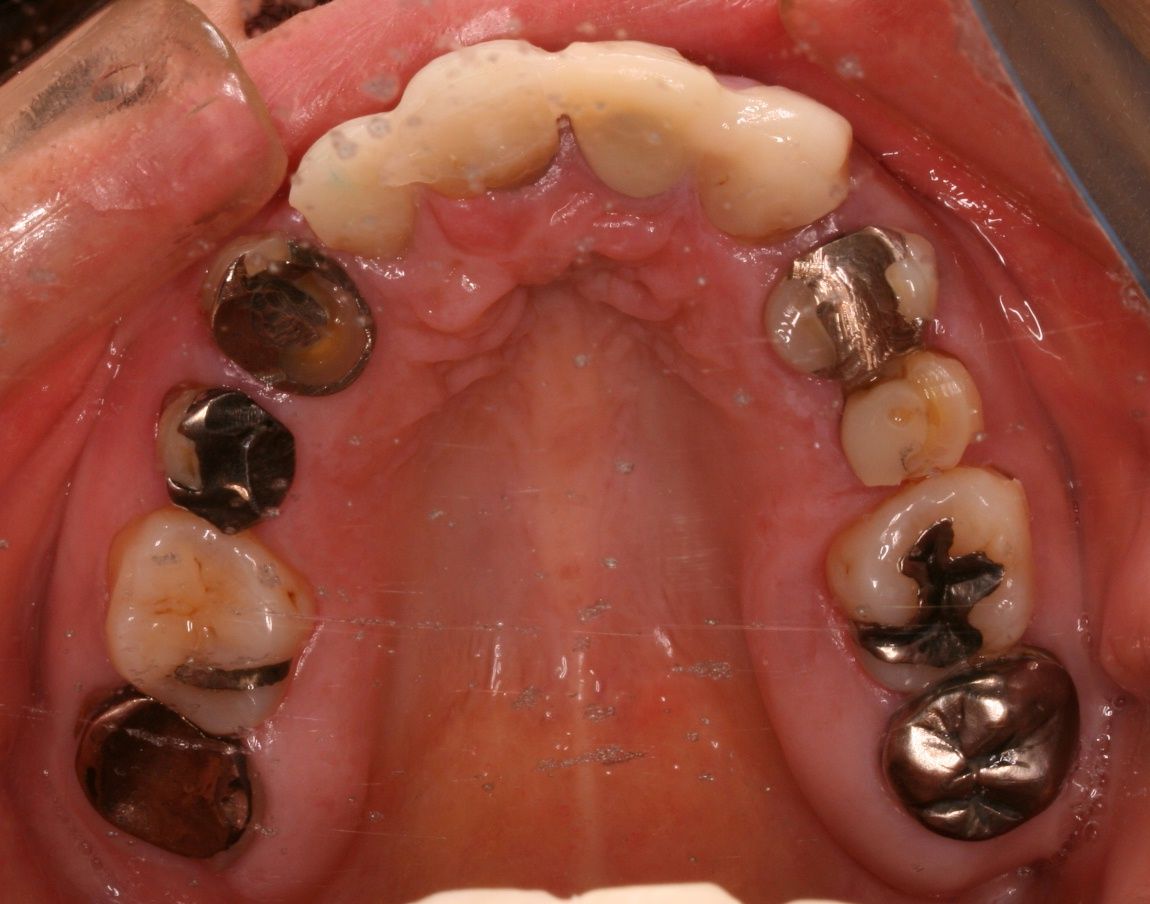

上から見ると、前歯はブリッジとなっており、左右1本づつ歯が欠損しております。

つまり、歯を抜いたのが左右1本ずつで、残りの歯をけずってブリッジにしております。

このような患者さんの場合、もし矯正をするならば、ブリッジにしない方向で隙間を閉じてあげることができないかどうかを検討します。